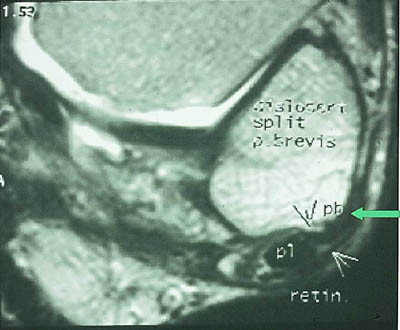

Mesteparten av sinus tarsi er fylt med fett. Dette gir høysignal på T1-vektet sekvensog lavsignal på fettsuppresjonssekvenser. Blodkar og nervefibrer gir små punktformige lavsignaler medialt i fettvevet på T1-vektet sekvens. Ligamentene gir lavsignal på spinnekkosekvensene. Figur 1 viser en normal sinus tarsi. I koronalplanet sees ligamentum cervicale ventralt og ligamentum interosseus noe lenger dorsalt. Det mest fremtredende og hyppigste MR-funnet ved sinus tarsi-syndrom er lavsignalområder på T1-vektet sekvens og lav- eller høysignalområder på T2-vektet sekvens. Forandringene er forårsaket av fibrose (fig 2) med eller uten inflammasjon (fig 3). Av og til kan vi se små væskelokulamenter som representerer ganglioncyster (fig 4). Ligamentene kan være vanskelig å se, enten fordi det er mye inflammasjon eller fordi de er røket. Hos en del pasienter kan man finne ruptur av laterale ankelligamenter, spesielt ligamentum talofibulare anterior.

I tillegg til å kunne påvise patologiske forandringer i sinus tarsi kan vi påvise andre årsaker til smerter lateralt i bakfoten: Osteokondrale skader ved øvre laterale talushjørne, avaskulære nekroser og stressfrakturer i omliggende knokler samt patologi i omliggende ligamenter og sener (fig 5) og (fig 6).